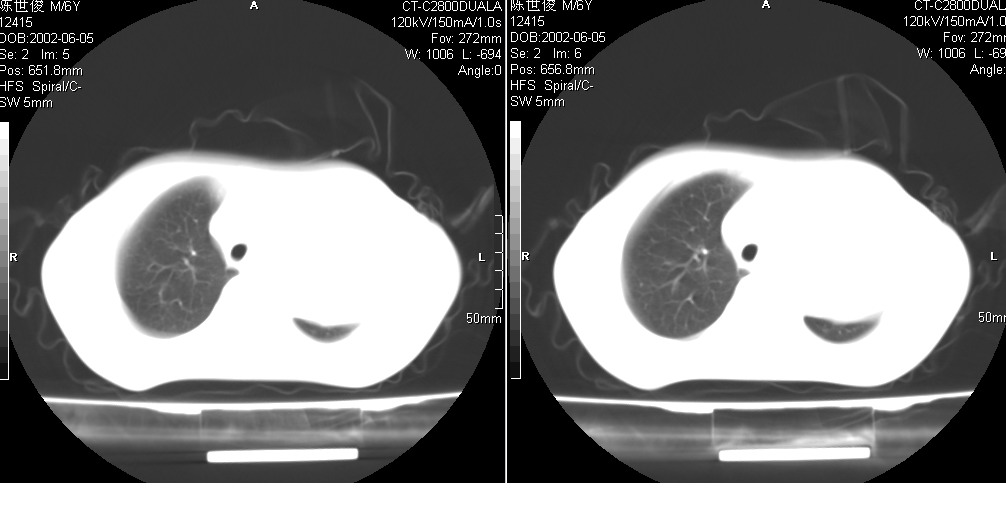

以下是引用xxhwh在2008-6-10 18:40:00的发言:[br]男,6岁,无规则发热一月余,体温在37.8——39度之间。一月前拍胸片示左上肺密度增高影,进行抗炎治疗8天,复查胸片未明显吸收。又改变抗菌素继续治疗半月,照胸片示病灶吸收不明显,行ct检查[br]征象:左上肺前段呈密实影,内可见支气管气像,远侧见絮状模糊影,中上纵隔左移。[br]意见:左上肺前段膨胀不全及感染,考虑为支气管异物或支气管内膜结核所致,[br]建议追问有无异物吸入史,行痰检及ppd检查